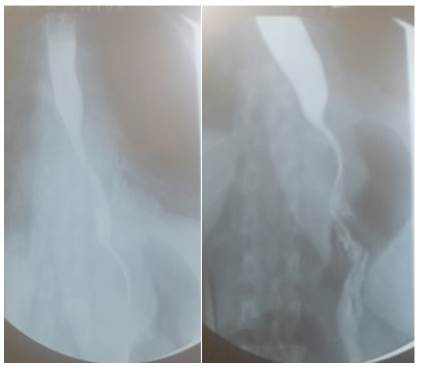

Dos días después, una radiografía control reportó normalidad del tránsito esofágico, del estómago y del bulbo duodenal, sin fugas, se descartaron recidivas y se verificó unión gastroesofágica permeable (figura 4).